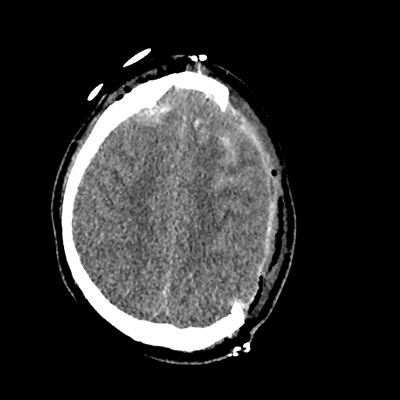

On day 5 of admission, he begins having intracranial hypertension again, spiking up to 40mmHg. You bolus with propofol and fentanyl, to no avail. You then push 30mL of 23.4% NaCl, which provides some brief improvement, allowing you to quickly get a non-contrast head CT. Unfortunately, he's now back up to 36mmHg. You review his labs, and note the following: Na 150, K 3.8, Cl 119, HCO3 18, BUN 21, Cr 0.85, glucose 136, sOsm 320.

NCHCT

NCHCT 2/20 2/20